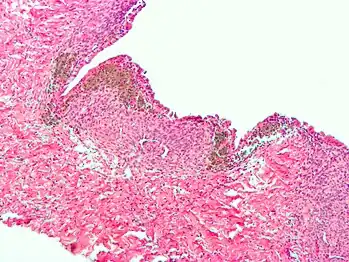

Micrograph showing endometriosis (right) and ovarian stroma (left)

Micrograph of the wall of an endometrioma. All features of endometriosis are present (endometrial glands, endometrial stroma and hemosiderin-laden macrophages).